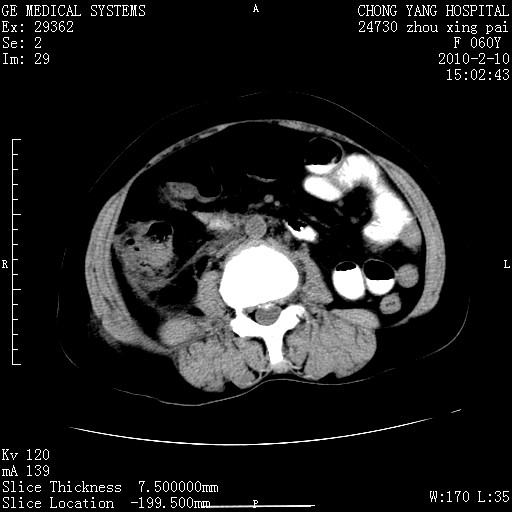

胆总管末端梗阻!结石?胰腺影增粗,以胰腺头部为著,胰周看见渗出影,双侧胸腔积液,(胸膜反应)考虑胰腺炎。

1)胆总管末端梗阻,不排除结石所致可能。2)胰腺炎。3)慢性胆囊炎可能。4)左侧输尿管上段扩张。5)少量腹水。6)双侧少量胸腔积液,伴两下肺部分肺萎陷。

1)胆囊炎。2)胆源性胰腺炎。3)右肾周筋膜增厚,肾旁前间隙积液。4)左侧输尿管上段扩张。5)少量腹水。6)双侧少量胸腔积液,伴两下肺部分肺膨胀不全。

1)胆总管末端梗阻。2)胰腺炎。3)慢性胆囊炎可能。4)左侧输尿管上段扩张。5)少量腹水。6)双侧少量胸腔积液,伴两下肺部分肺萎陷。